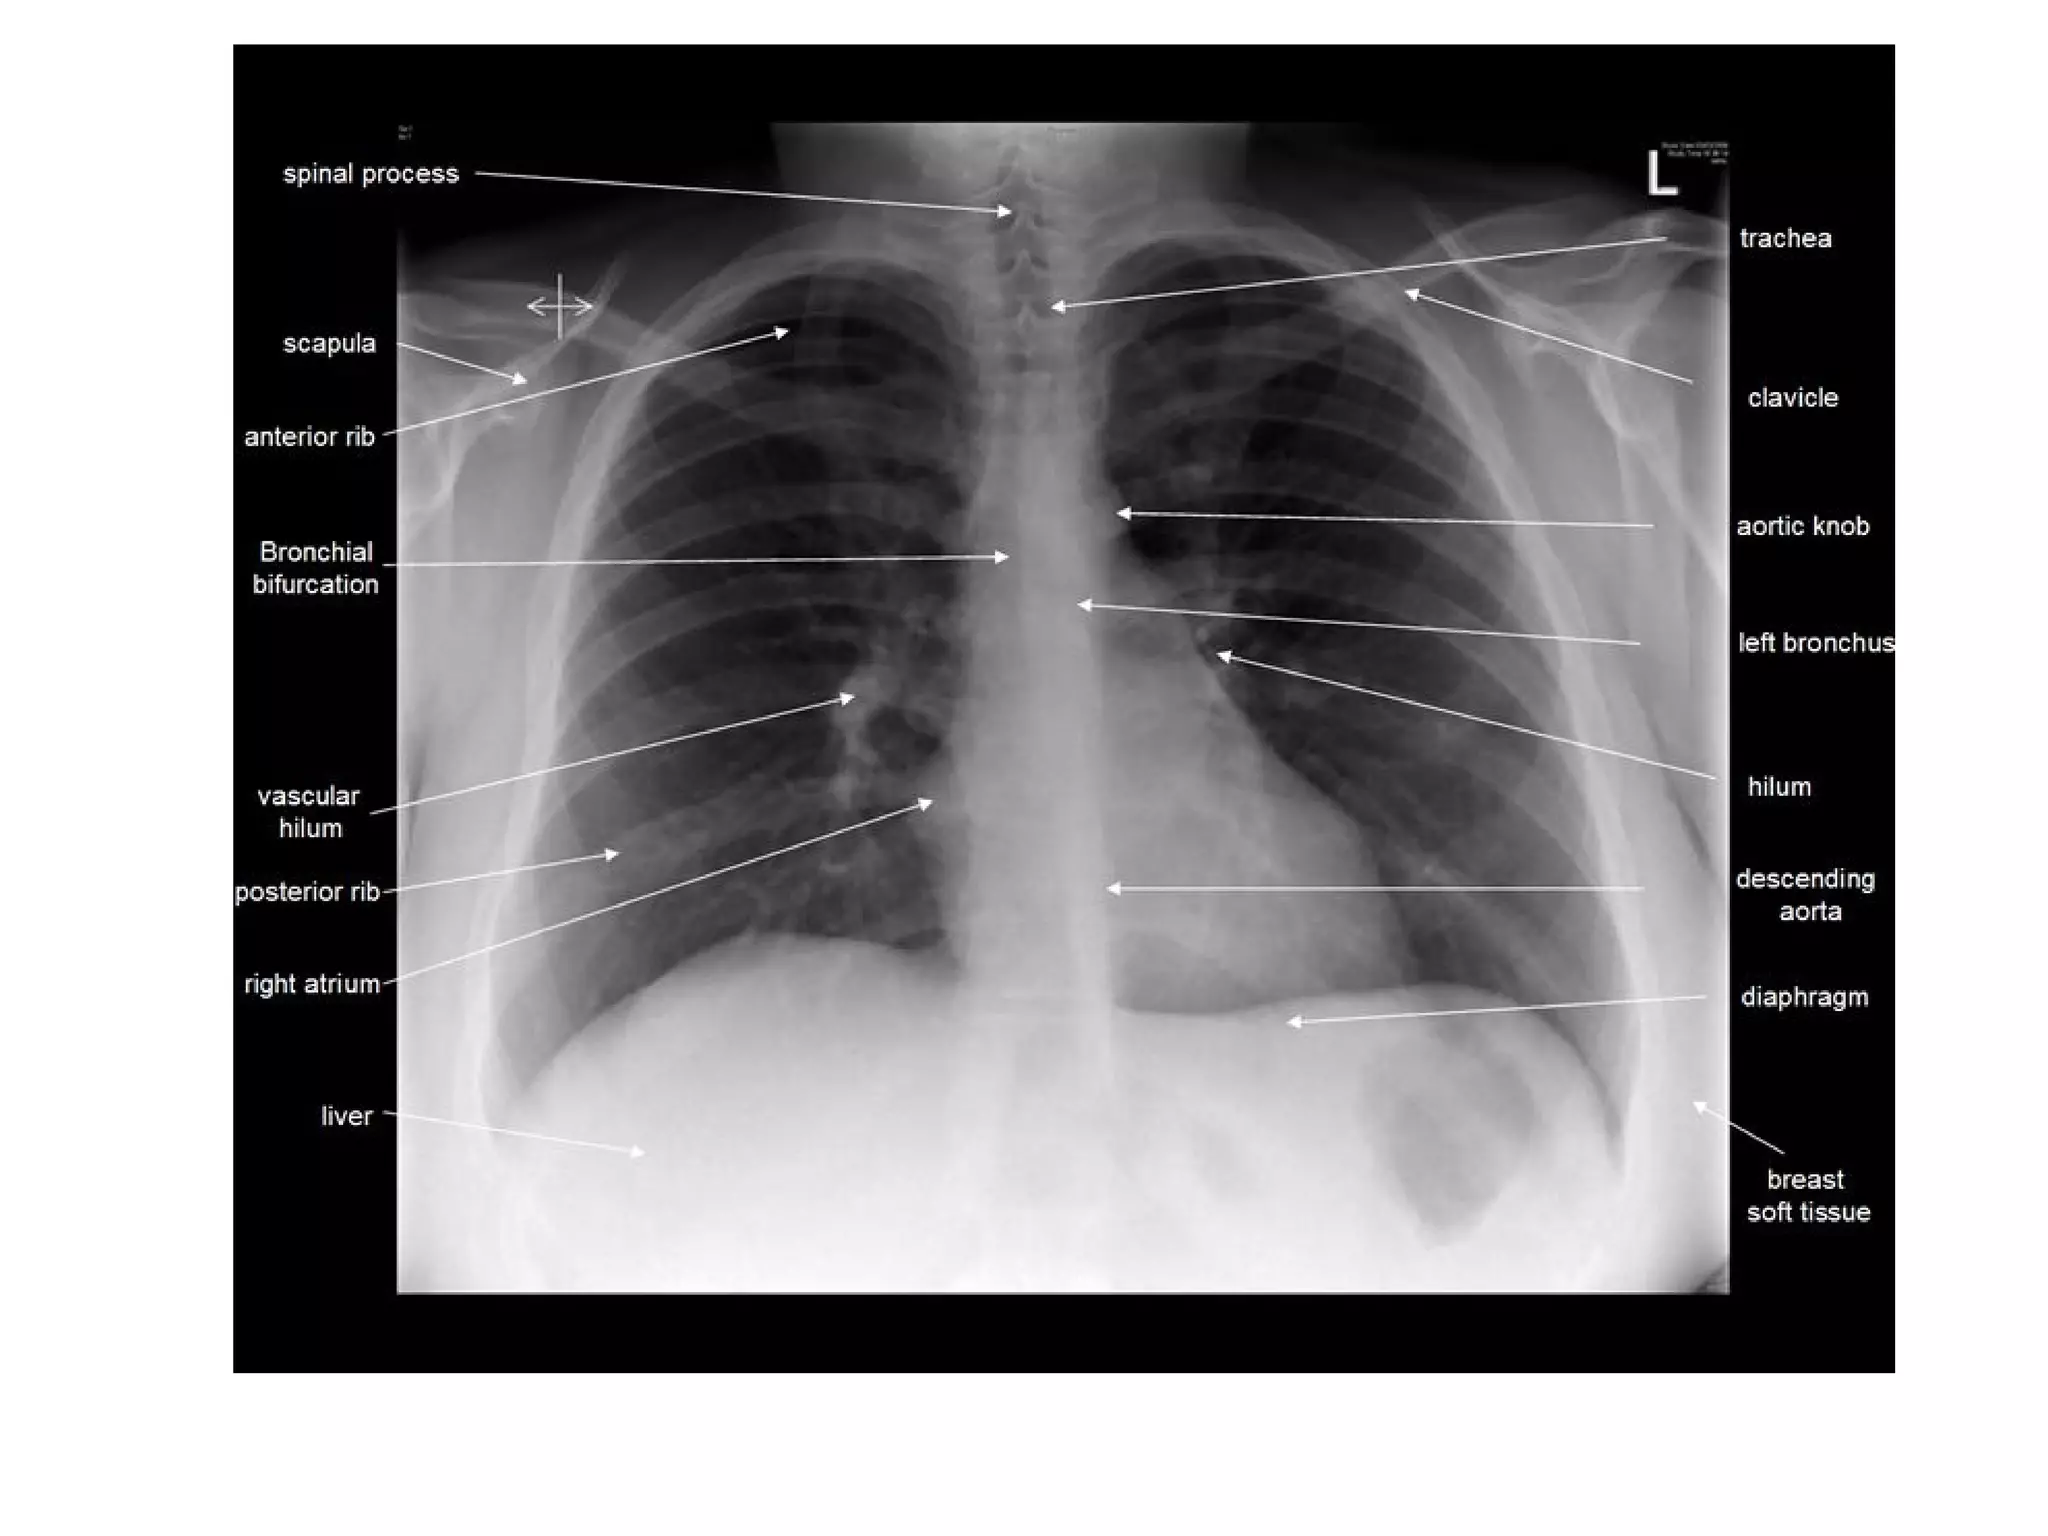

The mediastinum and heart

The central dense shadow seen on PA CXR

comprises the mediastinum, heart, spine and

sternum

The cardiac shadow lies to the left of the midline

and 1/3 to the right although it is quite variable

The transverse cardiac diameter normal for female

< 14.5 cm and for males < 15.5 cm.

The normal cardiothoracic ratio is < 50% on PA

film and < 60% in AP film.

An increase in excess of 1.5 cm in the transverse

diameter on comparable serial films is

significant.

All borders of the heart and mediastinum

should be clearly defined

The mediastinum andheart The central dense shadow seen on PA CXR comprises the mediastinum, heart, spine and sternum The cardiac shadow lies to the left of the midline and 1/3 to the right although it is quite variable The transverse cardiac diameter normal for female < 14.5 cm and for males < 15.5 cm. The normal cardiothoracic ratio is < 50% on PA film and < 60% in AP film. An increase in excess of 1.5 cm in the transverse diameter on comparable serial films is significant.

All borders ofthe heart and mediastinum should be clearly defined In babies and young children the normal thymus is a triangular sail shaped structure with well defined borders which may be wavy.